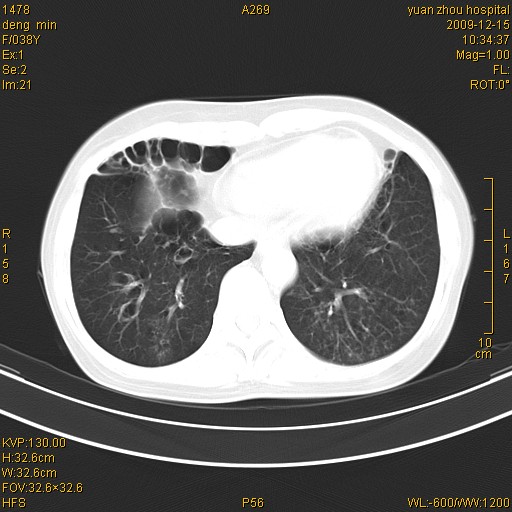

标题: CT23919:F38Y 咳嗽月余 [打印本页]

标题: CT23919:F38Y 咳嗽月余

支气管扩张。典型。

右肺中下叶、左肺上叶舌段及左肺下叶支气管扩张合并感染。